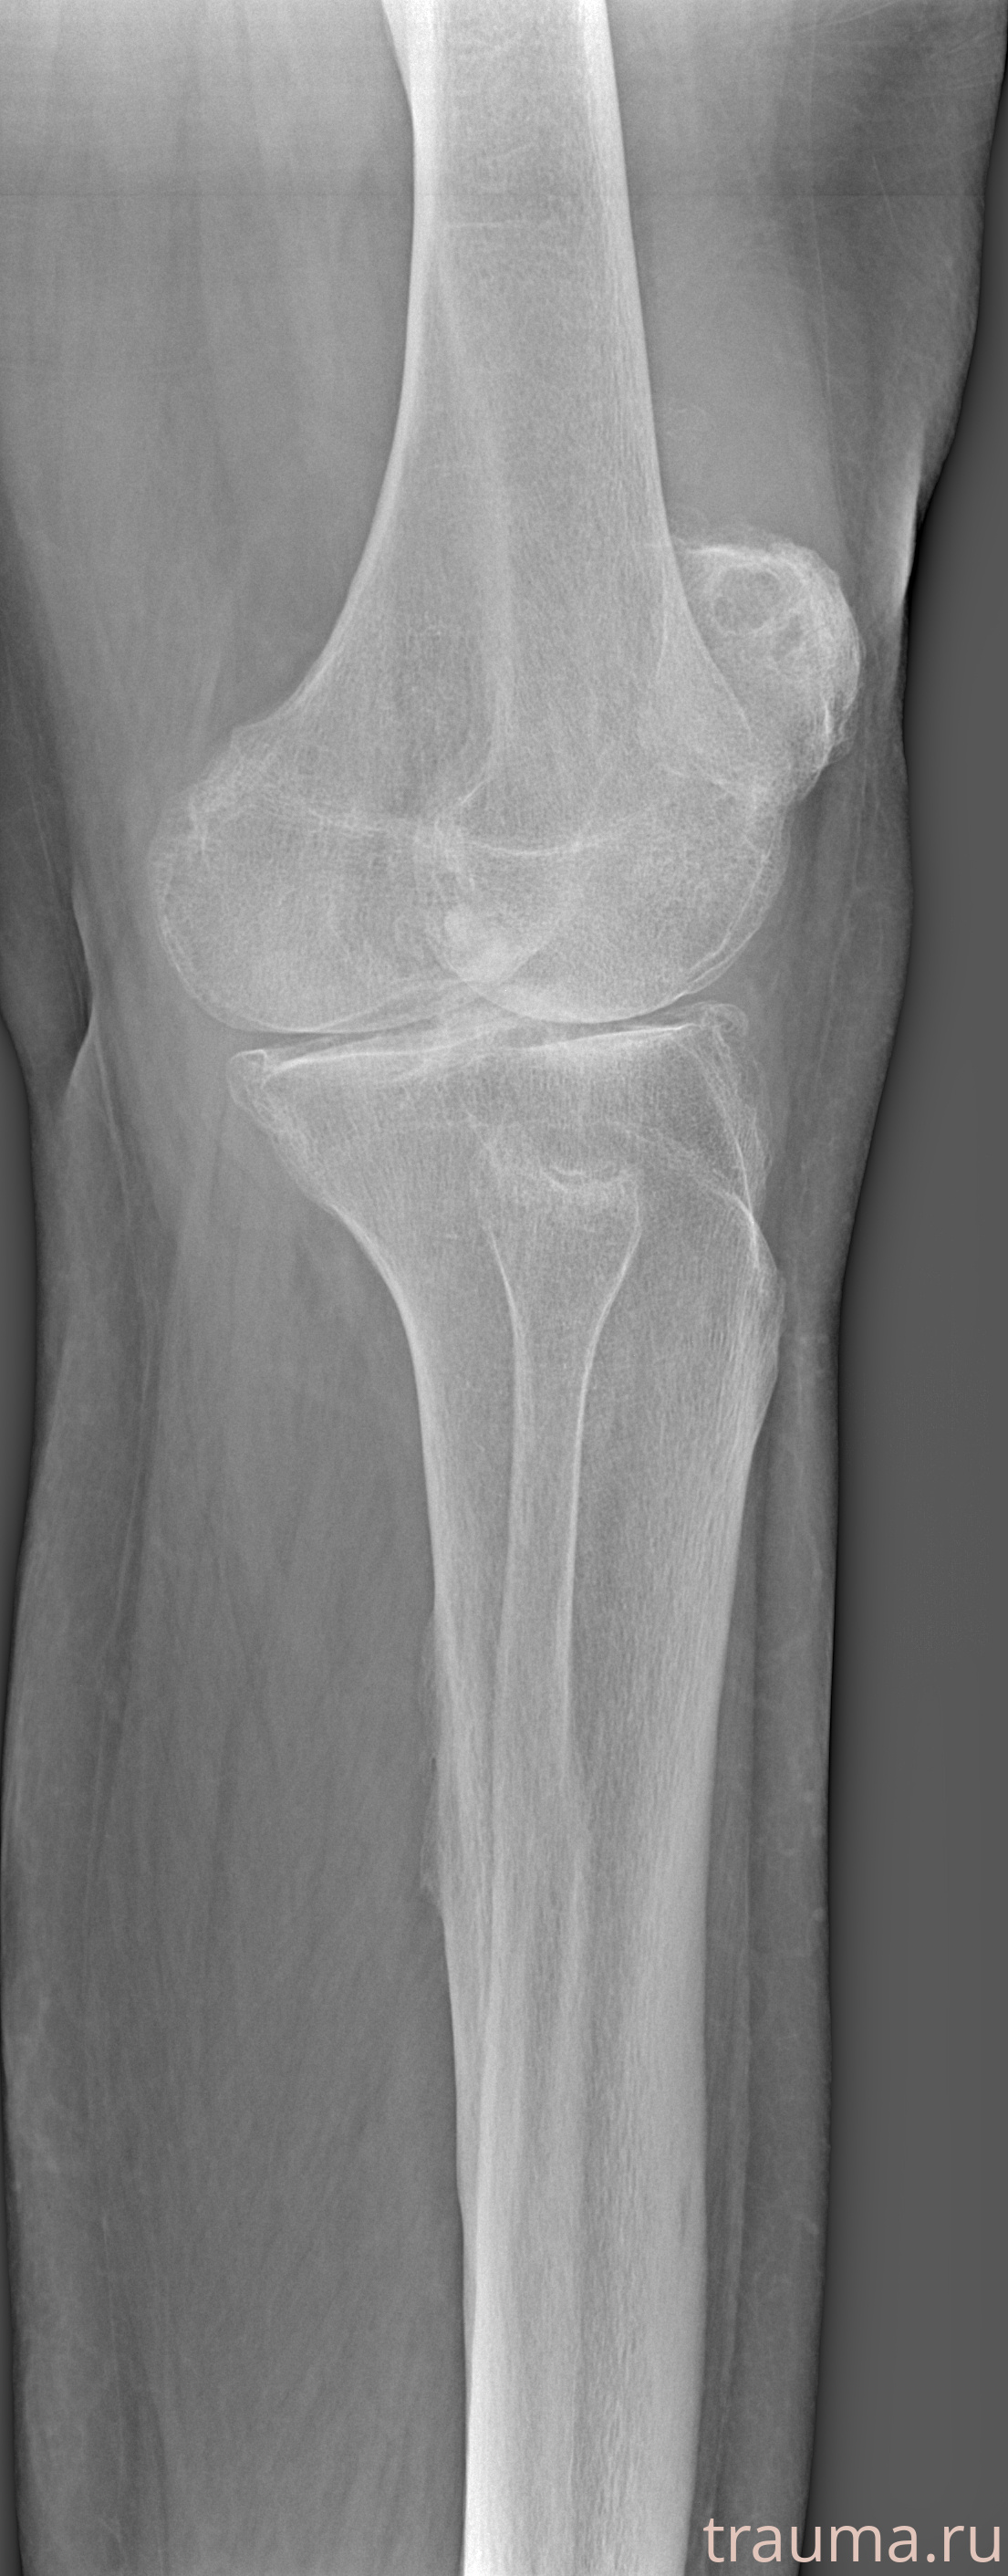

Рентгенограммы

Рентген на дому: по вашему адресу приезжает врач-рентгенолог, травматолог-ортопед с мобильным рентгеновским аппаратом, проводит диагностику травмы или заболевания, делает необходимые рентгенограммы, дает рекомендации по дальнейшему лечению. Получить качественные снимки в домашних условиях возможно благодаря уникальной методике, разработанной МосРентген Центром для института  Склифосовского